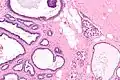

Collagenous spherulosis is characterized by a tubular/cribriform architecture with intratubular eosinophilic material that classically is arranged like the spokes of a wheel ("radial spikes"). There is usually no mitotic activity, and two cells populations (epithelial & myoepithelial) are present, like in benign breast glands.

The lesions are typically small (less than 50 spherules per lesion, less than 100 micrometers in size) and may be multifocal.

Intermed. mag.